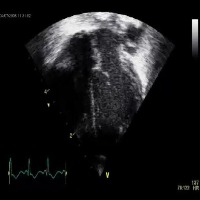

Medical Diagnostics: Medical professionals can employ the "echo_structures" model to improve patient care by facilitating the identification and analysis of cardiac structures via echocardiogram (ultrasound) images to provide a quicker and more accurate diagnosis of cardiovascular diseases and conditions.

Personal Health Monitoring: Integration of "echo_structures" model with mobile health apps and wearable devices (such as smartwatches) could allow for continuous and real-time monitoring of cardiac health, identifying abnormalities or potential concerns, and alerting users or healthcare providers when intervention may be needed.

Telemedicine Support: The "echo_structures" model could be incorporated into telemedicine platforms to assist remote medical professionals in diagnosing and treating cardiac conditions by allowing them to better understand patients' visual cardiac data and provide appropriate care from a distance.

Medical Research: Researchers in cardiology can utilize this model to efficiently process and analyze a large number of cardiac ultrasound images to study trends, monitor changes in heart structure or abnormalities, and support the development of novel medical approaches or innovative treatments for cardiovascular diseases.

Medical Training: The "echo_structures" model can serve as a valuable educational tool for medical students learning to read and interpret ultrasound images accurately. By automating the identification of cardiac structures, the model can provide immediate feedback, increasing students' learning efficiency and potentially improving overall diagnostic skills.